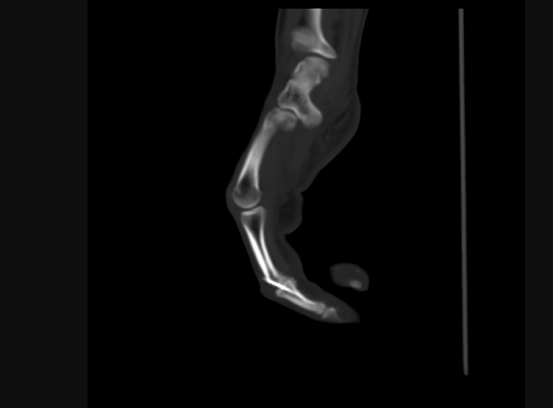

近日,45岁刘先生在工地工作时,由于操作不慎,被圆盘锯割伤右手,导致右手肿痛、严重出血,到我院接受治疗,经检查发现右中指关节缺损。9月30日,我院手足外科团队成功为其实施自体小关节移植修复术,在手外伤创伤修复领域迈出重要一步。